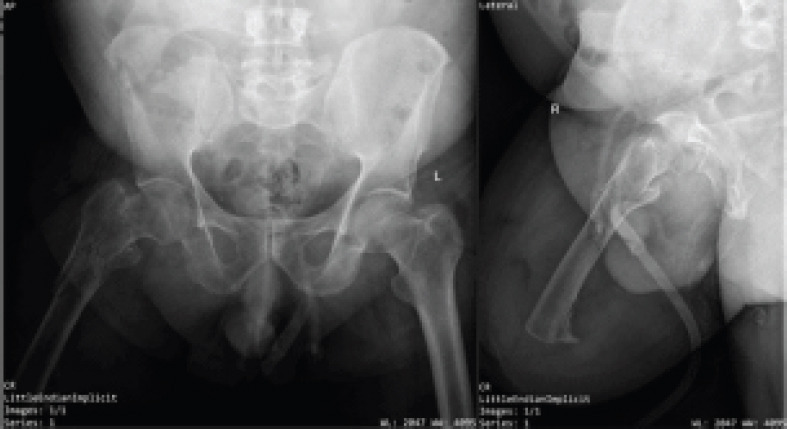

Case report: This report presents the case of an elderly male with a right above-knee amputation who sustained an ipsilateral IT fracture. He had undergone amputation 3 years prior and was mobilizing independently with a prosthetic limb. The current injury occurred due to the rollover of a four-wheeler in which he was traveling. A proximally sized femoral nail was selected for fracture fixation, with the goal of internal splinting across the entire residual femoral length. Postoperatively, the patient resumed use of his previous prosthesis without difficulty.